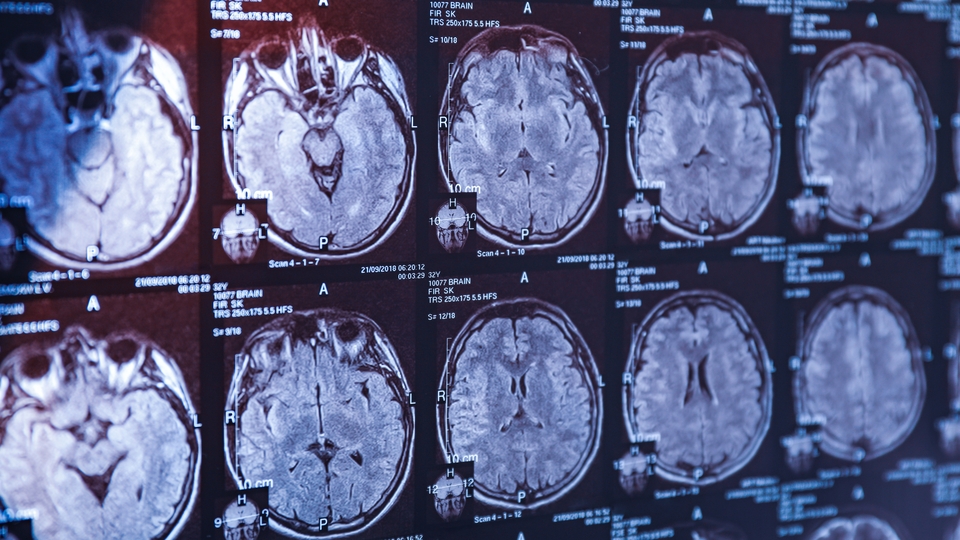

Yeni bir araştırma, yaşlı erkeklerde yaygın görülen bir genetik varyantın demans riskini ciddi şekilde artırabileceğini ortaya koydu.

Araştırmada, ABD ile Avustralya'da yürütülen ve kalp-damar hastalığı, demans ya da bilişsel gerileme geçmişi olmayan yaşlı bireyleri takip eden çalışmaların verilerinin kullanıldığı bildirildi.

Araştırmacılar, Avrupa kökenli 70 yaş üzeri 12 binden fazla Avustralyalı üzerinde HFE genindeki varyantlara odaklandı.

Bu gen, vücuttaki demir seviyelerini düzenlemede kritik rol oynuyor. Özellikle ‘H63D’ isimli varyantın iki kopyasına sahip erkeklerde, demans gelişme riskinin 2,39 kat daha yüksek olduğu belirlendi. Bu risk artışı, yalnızca erkeklerde görülürken kadınlarda benzer bir ilişki tespit edilmedi.

Araştırmaya göre bu genetik yapı, ‘hemochromatosis’ adı verilen ve vücutta aşırı demir birikmesine yol açan bir duruma neden olabiliyor. Bu durum da karaciğer sirozu, karaciğer kanseri, kas iskelet sistemi sorunları ve demans gibi hastalıklarla ilişkilendiriliyor.